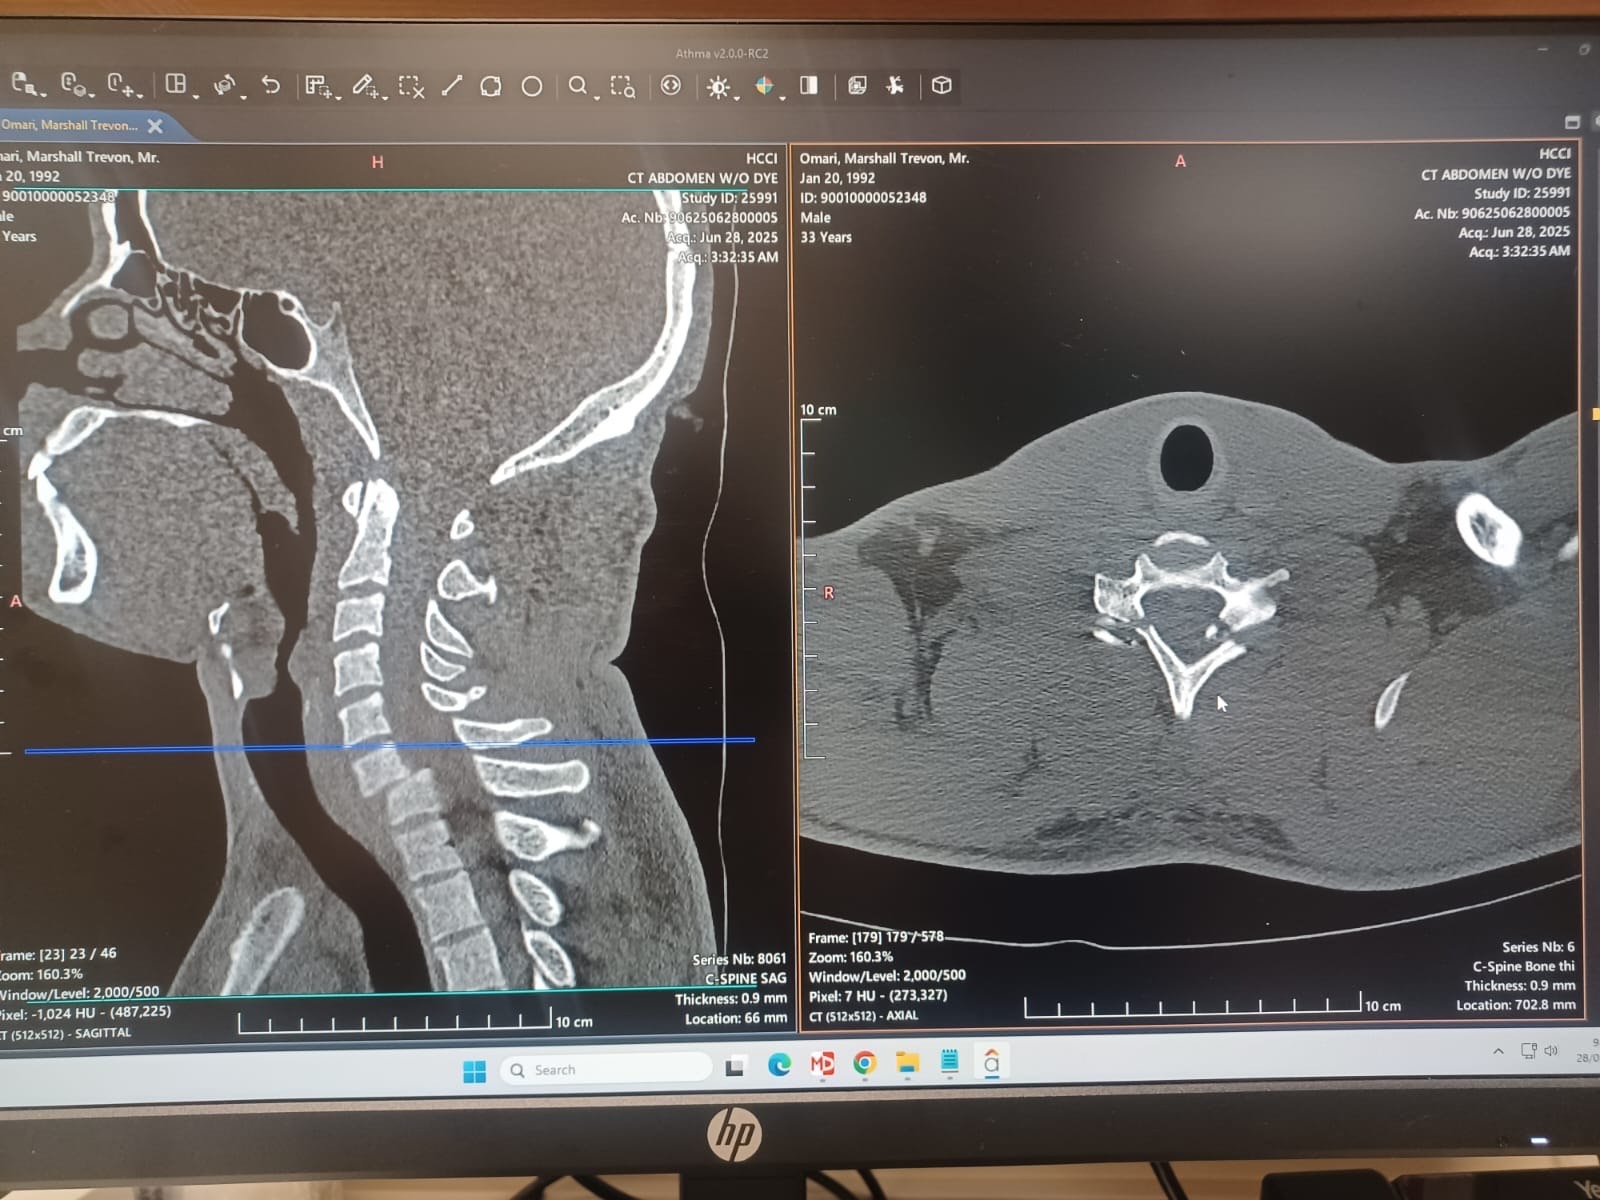

On June 27th, Omari Marshall (son of the late Sandra McKay) sustained life-threatening injuries in a serious car accident and had to be airlifted to Health City Hospital in the Cayman Islands. The circumstances have placed an overwhelming financial burden on our family, with escalating costs for the emergency airlift, surgery, and the critical postoperative care and rehabilitation he will require (estimated to be well over $166,000.00 USD).